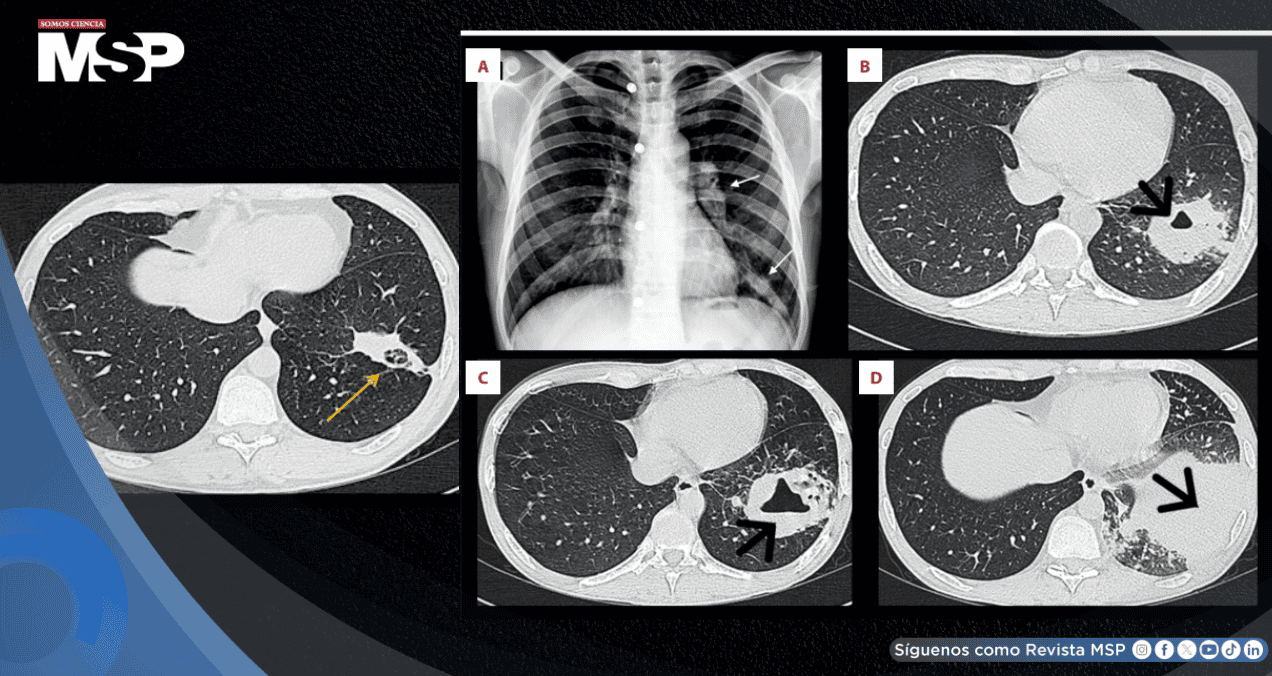

La radiografía de tórax mostró adenopatía hiliar izquierda y una opacidad mal definida en la zona inferior del pulmón izquierdo. Se solicitaron pruebas de VIH y estudios de bacilos acidorresistentes en esputo, pero no se realizaron ni recibieron seguimiento. Tampoco se tomaron hemocultivos.

La tomografía computarizada reveló una lesión cavitada de 55 por 41 milímetros en el lóbulo inferior izquierdo, acompañada de adenopatía hiliar izquierda y ganglios mediastínicos aumentados de tamaño.

Se programó una biopsia pulmonar que no se realizó por deficiencias en el seguimiento y coordinación. Tres semanas después, ante la persistencia de síntomas, se añadió levofloxacino. Sin embargo, a las siete semanas, una nueva tomografía mostró empeoramiento con una cavitación de 60 por 49 milímetros.

Aproximadamente cinco semanas después de iniciar la terapia antirretroviral, el paciente presentó nueva tos, fiebre y hemoptisis. La tomografía mostró empeoramiento con una consolidación cavitaria de 87 por 80 milímetros en el lóbulo inferior izquierdo, acompañada de nódulos, derrame pleural leve y adenopatías.

Actualmente, el paciente completa siete meses de tratamiento con moxifloxacino y linezolid orales. Una tomografía de seguimiento mostró marcada mejoría, con cambios fibróticos residuales. Ha regresado a trabajar y mantiene adherencia a la terapia antirretroviral, con CD4 de 221 células por milímetro cúbico y carga viral de 187 copias por mililitro.